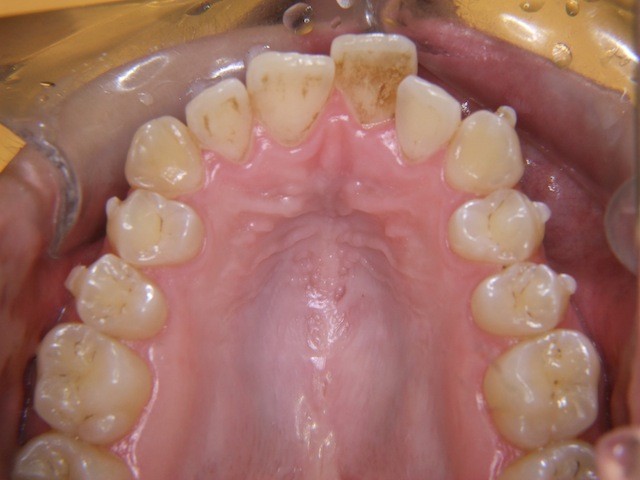

Beispiel einer Engstandsbehandlung bei einem Erwachsenen mit Invisalign

Vorher ----------------------------------- Nachher

Bilderserie Invisalignbehandlung Oberkiefer mit Stabilisierungsdraht am Schluss. Man beachte die Ansammlung von Belägen und Verfärbungen infolge Nischenbildung am Zahn der am meisten im Engstand steht.